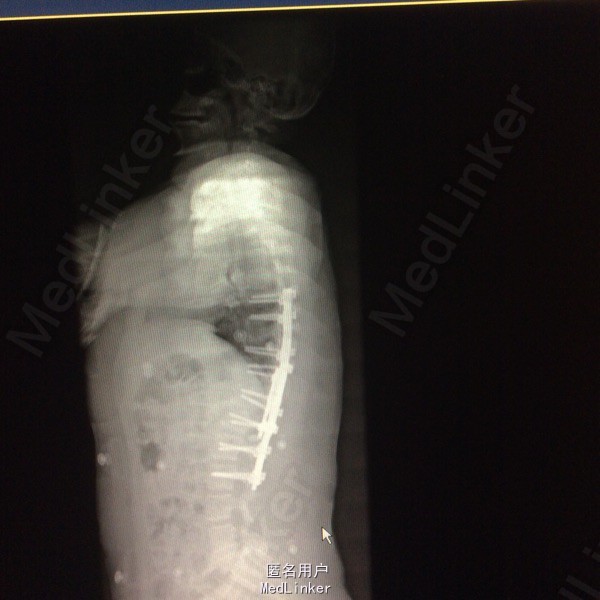

胸椎半椎体畸形 左侧第10肋骨缺如 隐形骶椎裂 双下肢膝外翻 双下肢肌挛缩症 脊柱畸形术,胸5、6、8、9腰1-2-3双侧椎弓根螺钉,去除胸11-12后方椎板,胸12半椎体及上下间隙间盘去除,椎间隙植骨。